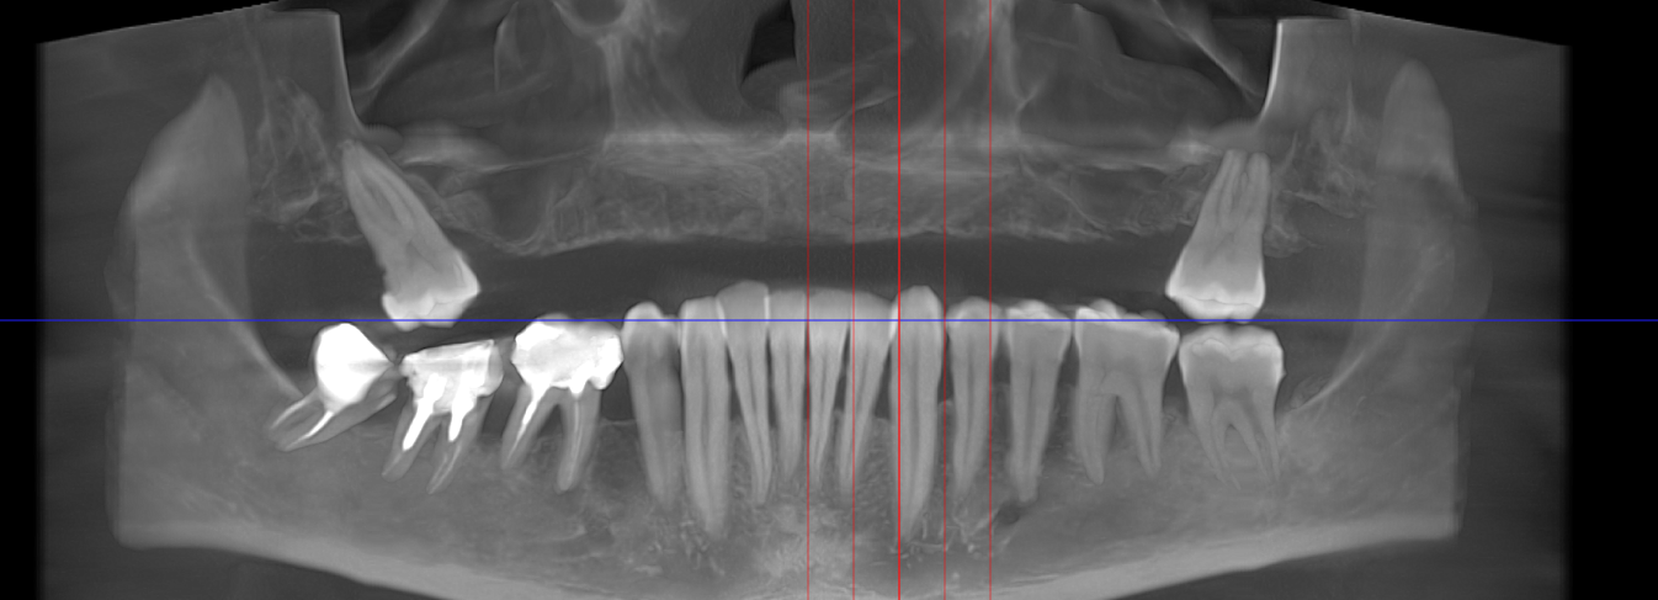

- Investigație imagistică completă, ideal CBCT (computer tomografie);

Această metodă este indicată pacienților cu edentație totală sau cu lipsuri dentare multiple, când dinții rămași nu mai pot susține o proteză fixă eficientă. Procedura se desfășoară în două etape:

Caz 1

Caz 2